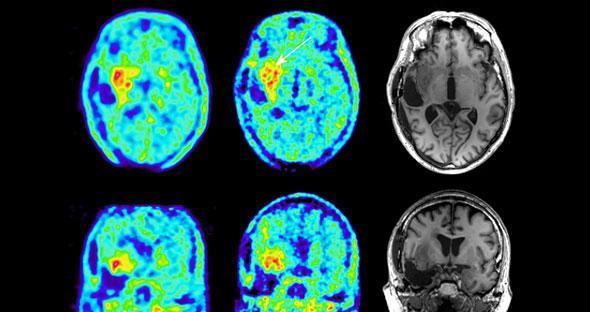

وعن انجاز سابع، زرع الأمل بقولب الملايين فقد سيطر العلماء على سرطان الدماغ من خلال إيجاد خلايا اصطناعية (النانو)، وبوضعها في الدماغ تساهم هذه الألياف بتجميع الخلايا السرطانية ومنع انتشارها، ليسهل استئصالها